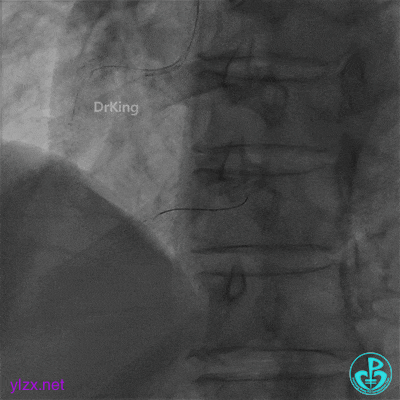

球囊扩张后血流中断

3.0×15mm双导丝球囊再次扩张。

双导丝球囊扩张后造影,血流缓慢,随即心率减慢至50次/分,血压降低至80/50mmHg,并出现短阵室速,随后意识丧失。